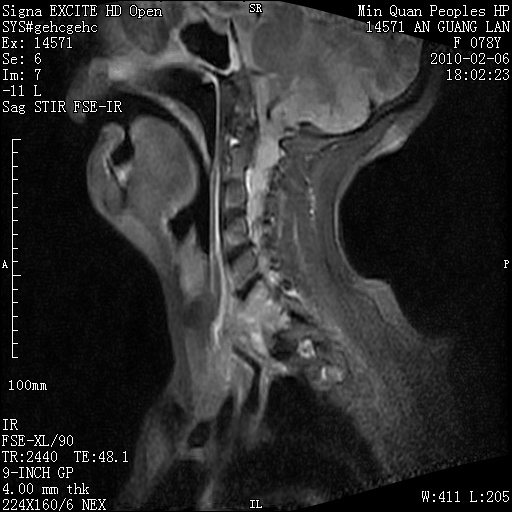

标题: MRI2763:C6、C7椎体病变性质?

f,78y,颈部与双上肢阵发性剧痛40余天。ct可见c6、c7椎体虫蚀样破坏,其间椎间隙变窄(没有图片资料可供上传)。

考虑椎体结核并椎旁脓肿。

考虑:c6/7椎体结核并椎旁脓肿形成,建议增强扫描。